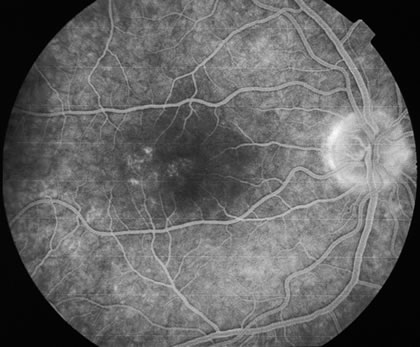

Fluorescein

The fluorescein angiograms of the white dots show a fine halo appearance in a wreath-like swirl configuration to some of the white dots, and this halo diffuses in the later stages of the angiogram, first developing a stippled pattern of fluorescence and then becoming a diffuse white spot that leaks only mildly. There may be leakage of fluorescein from the optic nerve and occasionally, there may be late staining of retinal vessels because of a mild vasculitis (Figs. 3 and 4).

Fig. 3. Venous phase fluorescein angiogram of fundus shown in Figure 1. It demonstrates the hyperfluorescent dots coalesced near the fovea and in a subtle wreath-like fashion elsewhere.

Fig. 4. Recirculatory state fluorescein angiogram of fundus shown in Figure 2. It demonstrates the leakage from the disc and the fluorescence of the white dots is more evident.